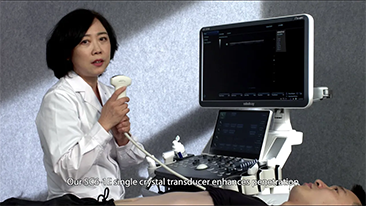

Menos preocupa??o com o estetoscĂłpio e mais com o ultrassom?

? necessĂĄrio otimizar fluxos de trabalho de obstetrĂcia e ginecologia para suportar grandes volumes na triagem da saĂșde da mulher. Por exemplo, as mĂĄs-forma??es do sistema nervoso central (SNC) s?o uma das anomalias congĂȘnitas mais comuns. Obten??o de imagens ruins devido Ă mĂĄ posi??o fetal, o MSP Ă© particularmente difĂcil de ser encontrado em um ultrassom 2D. Portanto, a detec??o e as medi??es automĂĄticas podem aumentar muito a eficiĂȘncia da realiza??o do exame.